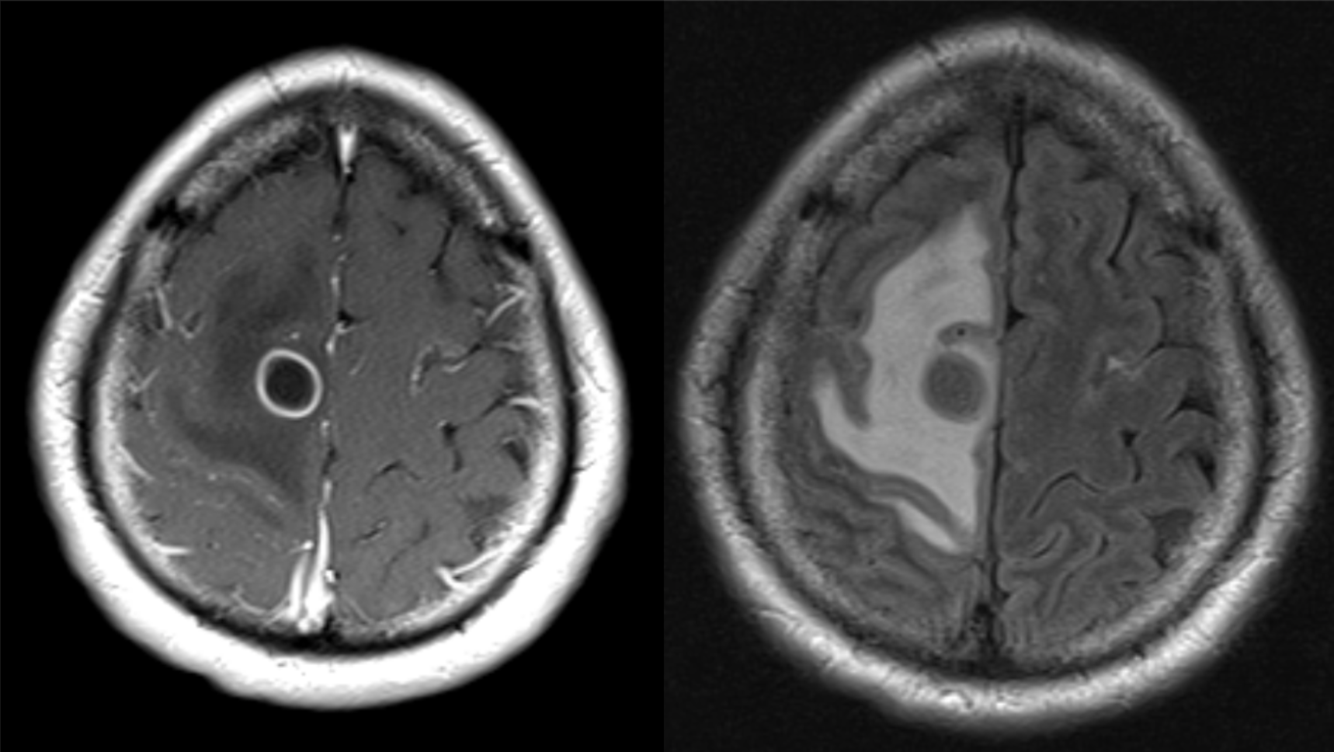

HIV patient with left-sided weakness.

Toxoplasmosis